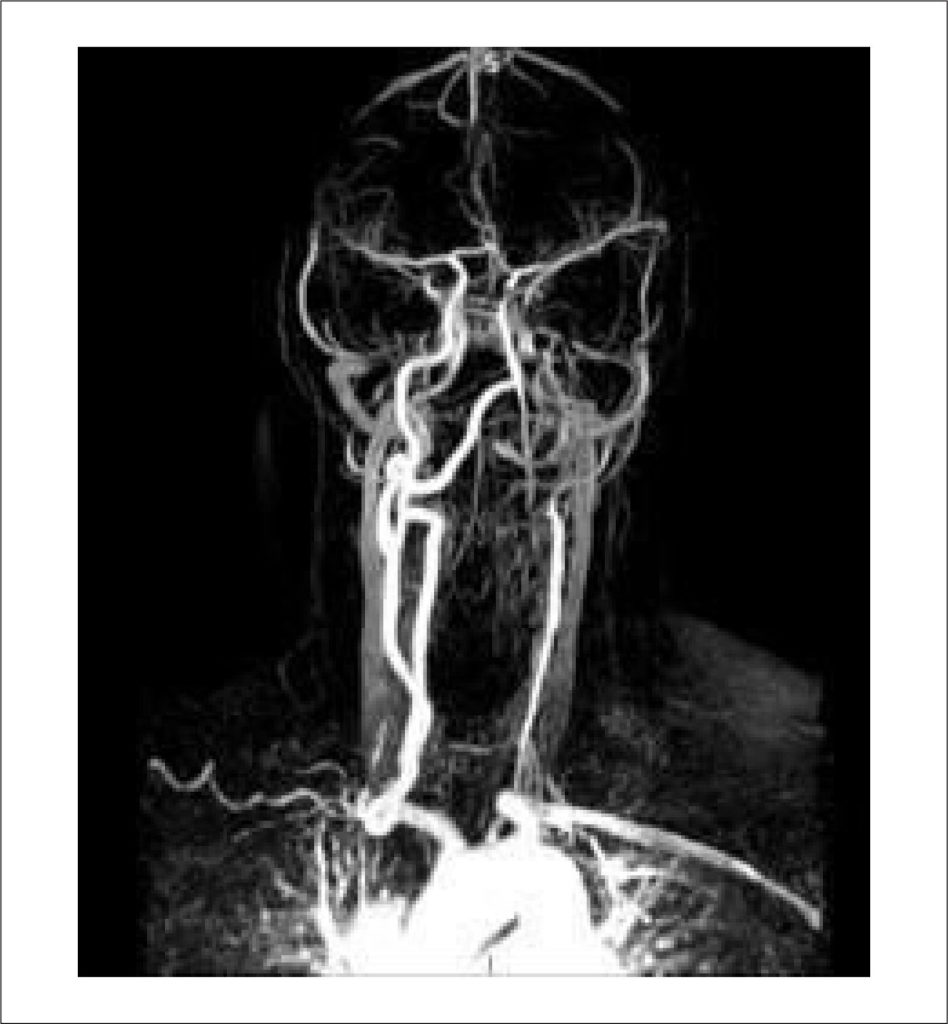

Neurological Manifestations of Takayasu Arteritis: A Case Report and Literature Review

Takayasu arteritis (TA) is a rare large-vessel vasculitis that primarily involves the aorta and its major branches and predominantly affects women of reproductive age. We report the case of a woman who experienced an ischemic stroke at age 20 and a transient ischemic attack at age 53, with TA diagnosed only after the second cerebrovascular event. Although ischemic stroke is an uncommon initial manifestation of TA, early recognition and timely management are essential to prevent further complications and improve long-term outcomes.